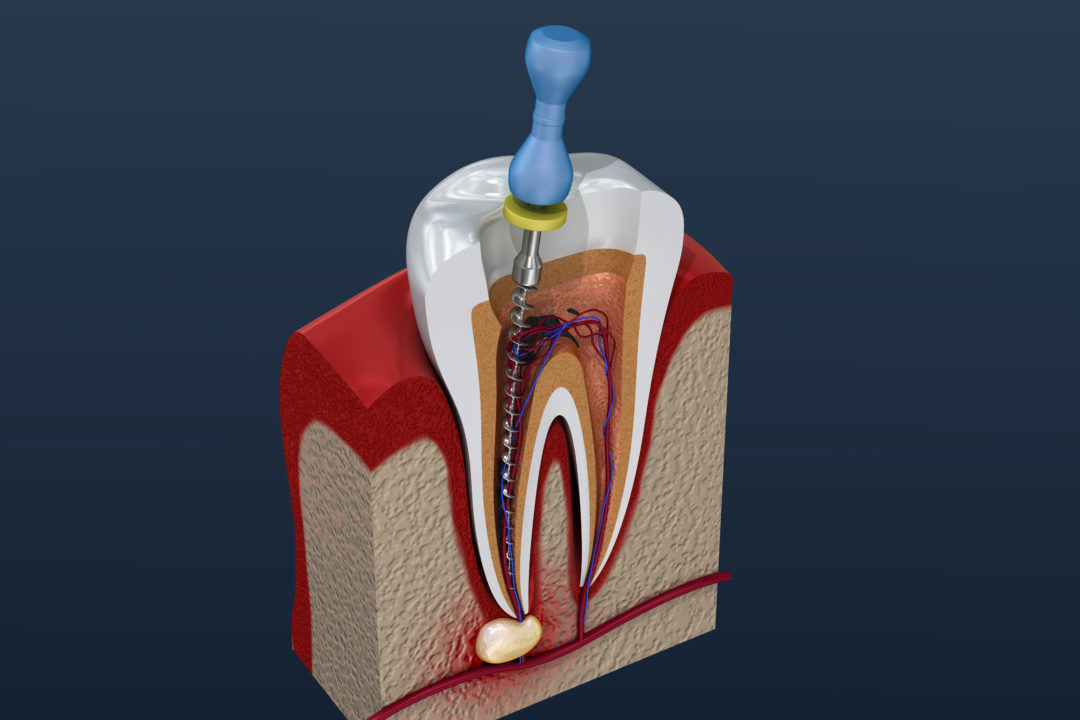

Wurzelkanalbehandlung

Ist der Nerv im Inneren des Zahnes abgestorben oder soweit erkrankt, dass eine Heilung nicht mehr möglich ist, so wird eine Wurzelkanalbehandlung notwendig. Dabei wird das Innere des Zahnes aufbereitet und gereinigt.

Diese Behandlung führen wir zum Erhalt Ihres natürlichen Zahnes durch. Folgende technische Hilfsmittel stehen in der Praxis zusätzlich bei der Behandlung zu Verfügung:

- Endometrie

Diese Technik ermöglicht eine Längenbestimmung ohne Röntgenaufnahme. Somit können wir die Anzahl der notwendigen Röntgenbilder reduzieren. - Digitales Röntgen

Trotz Endometrie sind bei der Wurzelkanalbehandlung Röntgenaufnahmen notwendig. Hierfür steht ein digitales Röntgengerät zu Verfügung, um die Strahlenbelastung für Sie so gering wie möglich zu gestalten. - Mikroskopgestützte Behandlung

In unseren Räumen am Postplatz bieten wir Ihnen die Möglichkeit, komplexe Wurzelkanalbehandlungen unter dem Mikroskop von Frau Vogt durchzuführen zu lassen. Hierfür steht ein Mikroskop der Firm Zeiss zur Verfügung. Durch diese spezielle Art der Behandlung lassen sich Wurzelkanalbehandlungen noch präziser durchführen, um Ihre natürlichen Zähne so lange wie möglich zu erhalten. Gerade Patienten, die eine Versorgung mit Implantaten ablehnen, bieten wir hier die Option, alles zu unternehmen, um Ihren natürlichen Zahn so lange wie möglich zu erhalten.